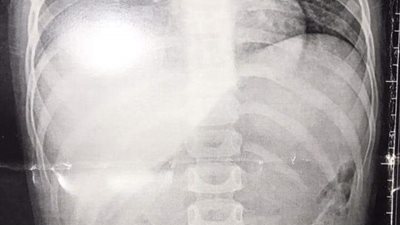

إنقاذ طفلة ابتلعت خرزة شخشيخة أطفال ببنها الجامعي